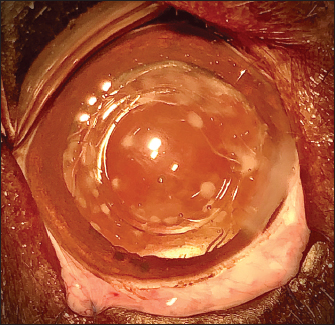

The APC was initiated by very gently making small perforations of the PC with a 30-gauge needle. Then, long curved Vannas scissors were inserted through this narrow posterior capsulotomy to cut PC to the right, removed from the eye, and then reintroduced for a cut to the left (Fig. 4). APC was then performed continuously with Utrata forceps, from one flap to the other to obtain a circular axial opening of about 3 mm diameter (Fig. 4). A slight anterior vitrectomy (Anterior Vitrectomy Probe w/21 GA Infusion Cannula, Alcon Laboratories, Inc. Fort Worth, USA) was then performed through the PC opening (under the IOL when initially placed) to prevent a possible vitreous presentation (Fig. 5). Using the irrigation/aspiration handpiece, IOL was the centered in the bag and viscoelastic removed. As mentioned above and depending on the case, the instruments (needle, Vannas scissors, Utrata forceps, vitreotome) were manipulated either with direct access to the PC thanks to the lateral positioning of IOL inside the capsular bag or in the space between the IOL optic and PC. The corneal wound was sutured by separate Polyglactin 910 absorbable stitches (Vicryl 9-0, Ethicon, Puerto Rico, USA). Administration of intracameral 25 mcg of tissue plasminogen activator (Actilyse, Boehringer, France) and 0.5 ml of 0.01% carbachol (Carbachol Intraocular Solution USP, Freedom Ophthalmic Pvt Inc, NY, USA) were achieved immediately after corneal incision closure in all cases. Methylprednisolone acetate (Depomedrol, Zoetis, Malakoff, France) was injected subconjunctivally at a dose of 5 mg in all cases, with no dog being diabetic.

Fig. 4. APC performed in the space between the IOL optic and the PC. Cutting of the PC to the right (a), then to the left (b). Removal of the central capsular opacity with the Utrata forceps (c).